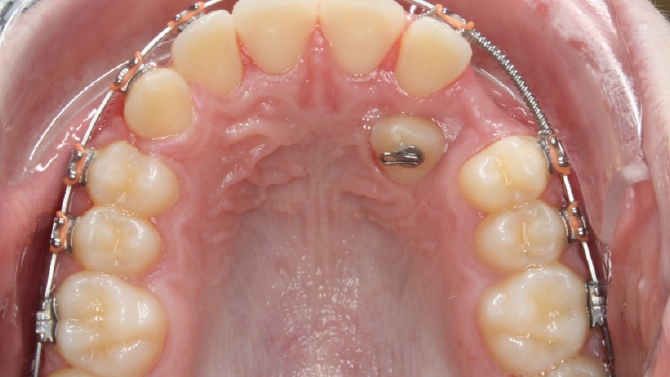

Pero algunas veces, los dientes definitivos no consiguen salir y quedan “retenidos” en el hueso por “debajo” de sus predecesores de leche. Esto se conoce con el nombre de diente incluido o retenido.

En cuanto se diagnostica que hay un diente incluido, es necesario estudiar con detalle el caso, ya que muchas veces lo más indicado es abrirle espacio mediante la ortodoncia y posteriormente llevar el diente incluido a su posición correcta en boca.